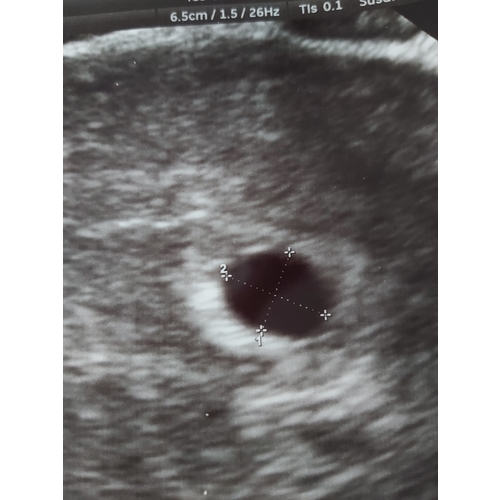

Dit was 5 weken ong en ik kon niet veel zien maar wel iets gelukkig 9 juni weer een echo hopen op een kloppende hartje